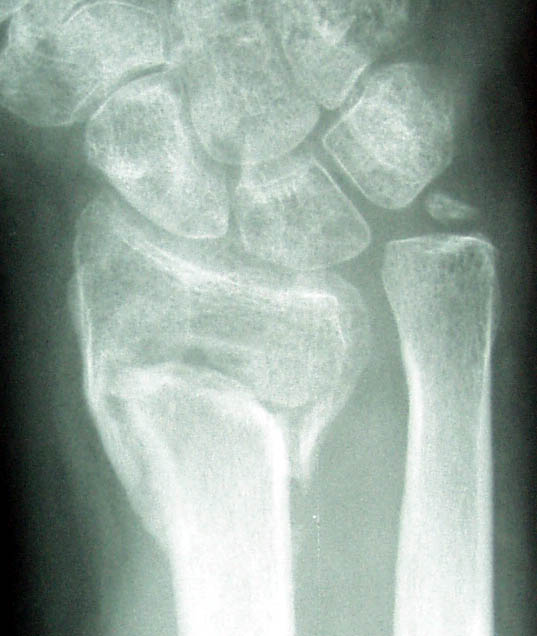

| Here are before and after xrays. Note that there is now more space between the arm bones and the wrist bones. | |

Before | After |